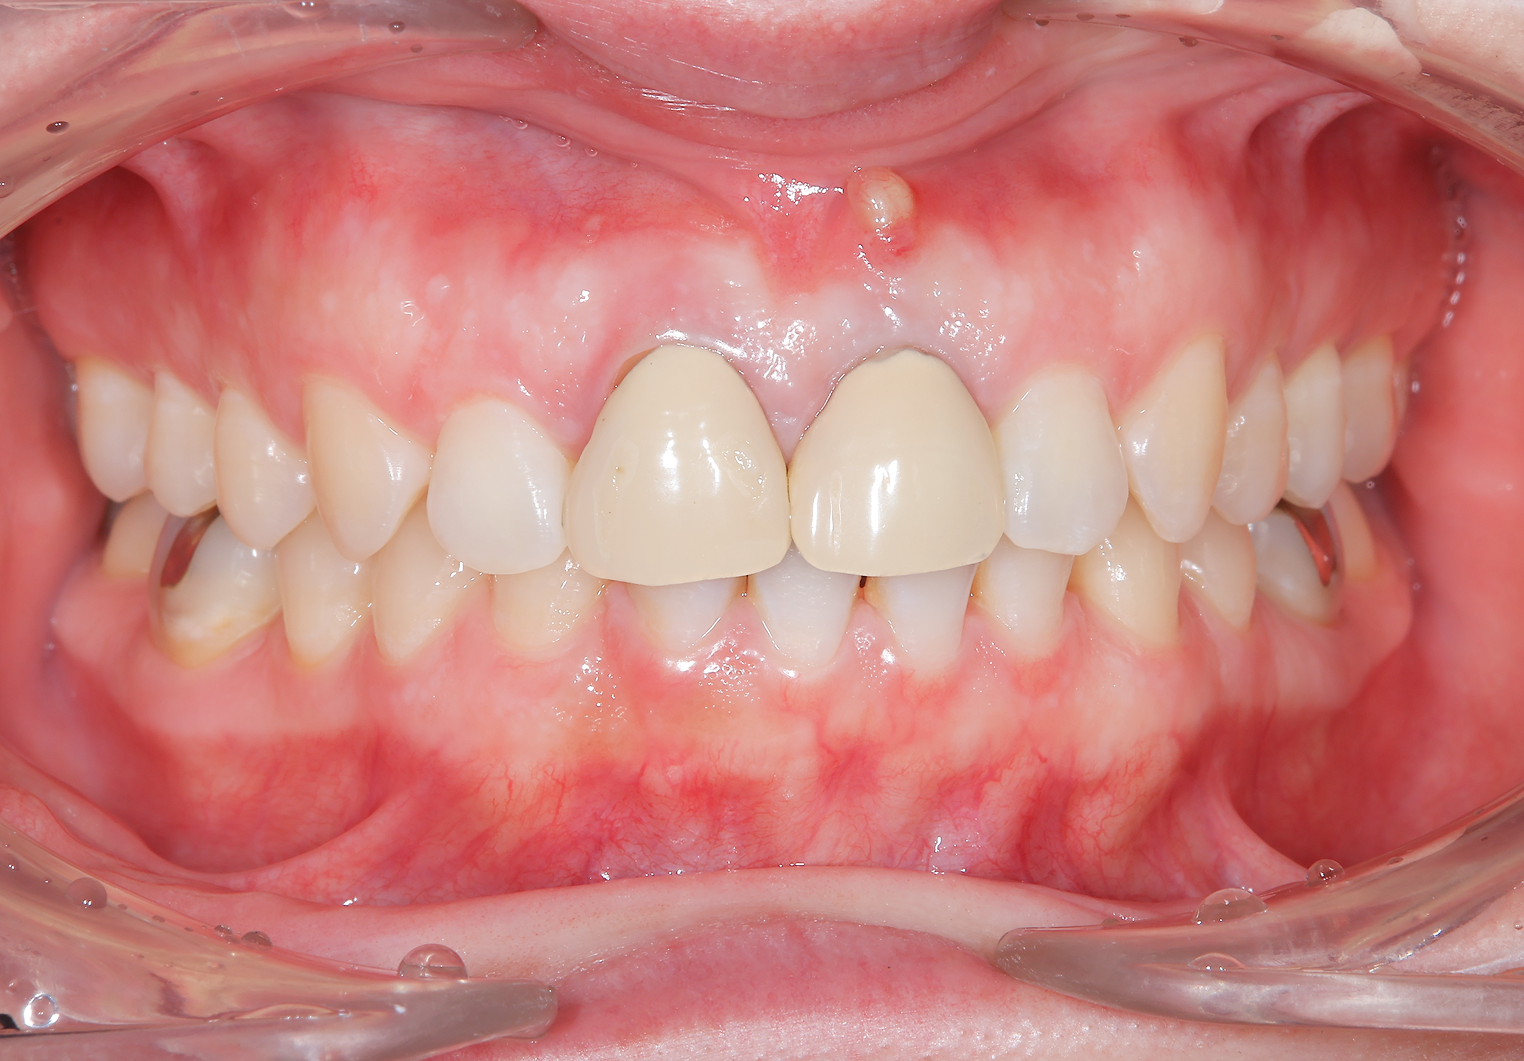

左上は歯の周りに骨が全然なかったので抜歯後に骨を作る処置(GBR)を行いました。

緑部分が作った骨になります。半年間待ちましたが、これがないと仕上がりが長い歯になってしまい、すごく見た目が悪くなってします。